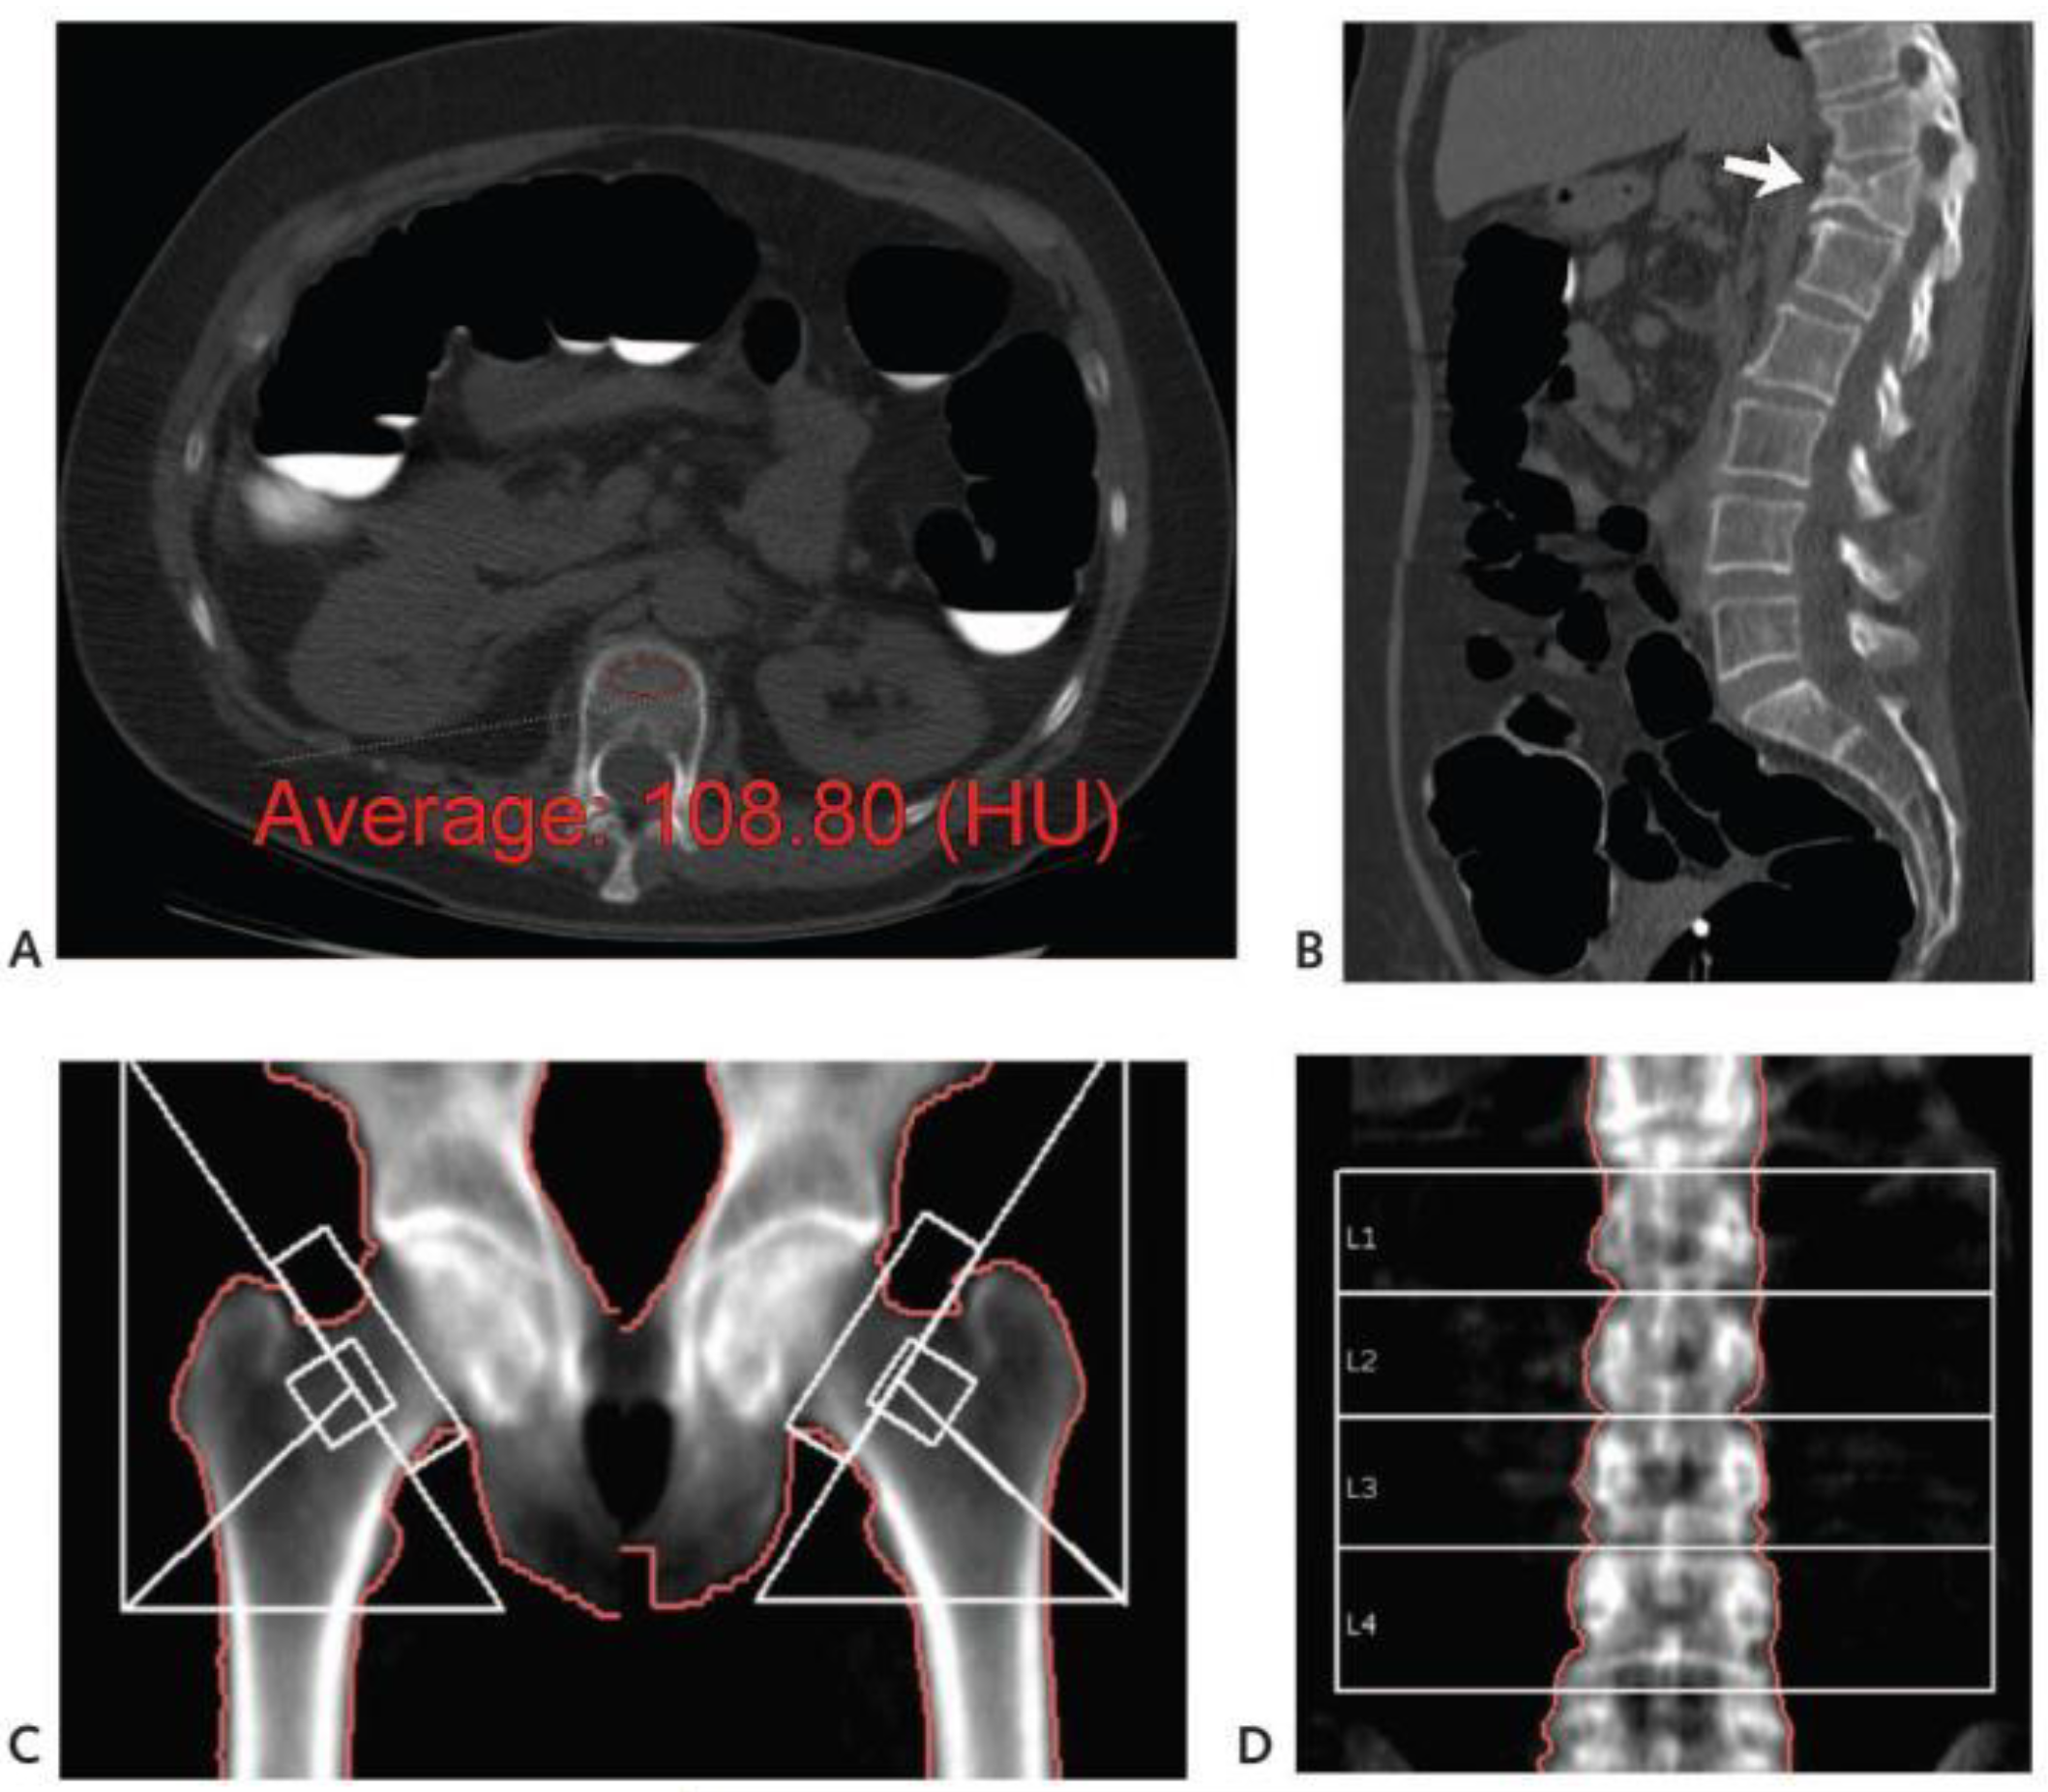

Some researchers have investigated studies on the loss of bone quality using CT scans by looking at CT scans on spinal weakening compared to readings from other methods such as DEXA. An illustration of the detection of weakened bone quality in the spine using a CT scan technique is shown in Figure 1. In their research, the bone quality was determined from the HU obtained from CT scan data, which was then compared with the standard DEXA method, as shown in Figure 1D.

Figure 1. Identification of bone quality based on the HU value of a CT scan. (A) axial; (B) sagittal, from abdominal CT scan with a moderate compression fracture (arrow). (C) pelvic bone; and (D) T-score from DEXA data where L1-L4 are a vertebral levels. [11].